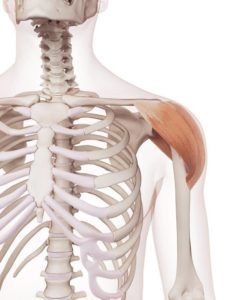

Deltový sval překrývá jako čepice ramenní kloub a je jeho nejpovrchovějším svalem. Tento sval dává ramenu tvar podle toho, jak moc je vypracovaný. Má tři části a jeho hlavní funkcí je upažení. Pro naše potřeby není nijak významně důležitý, problémy s ním jsou spíše ojedinělé. Pod ním se skrývají hlubší svaly, které mají úpon na hlavici kosti pažní a překrývají ji. Svými úpony pomáhají udržovat kloubní hlavici v jamce a jejich společnou funkcí jsou rotace a zvedání paže. Říká se jim rotátorová manžeta a můžete si je prohlédnout na obrázku číslo ???. Vnitřní rotaci zabezpečuje podlopatkový sval, který je zajímavý tím, že je umístěn na spodní ploše lopatky a je v blízkém kontaktu se žebry. Je velmi citlivý na dehydrataci, jejímž důsledkem může být pomyslné přilepení tohoto svalu na hrudník a horší skluznost lopatky po hrudníku, což má za následek horší hybnost paže. Zevní rotátory jdou z horní plochy lopatky na hlavici kosti pažní. Jmenovitě se jedná o sval nadhřebenový a podhřebenový a o malý oblý sval. Často se v nich vytvářejí bolavé body, takzvané trigger pointy neboli spoušťové body, které při stlačení působí bolest. Rotátorová manžeta je častým zdrojem chronických obtíží a není neobvyklé, že dochází k rupturám jejích svalů. Je to dokonce jedna z nejčastějších obtíží v této oblasti. Nejochotněji praská drobný sval nadhřebenový, který je v nevýhodné pozici svým umístěním. Nebudu zabíhat do zbytečných detailů, ale protože je to malý sval zastávající hodně práce, který je ještě navíc zavřený pod zobcovitým výběžkem lopatky, je doslova „na ráně“. Jeho prasknutí, byť jen částečné, může pěkně pozlobit bolestmi na přední straně ramene a omezením rozsahu pohybu právě do rotací. Zároveň bývá nadhřebenový sval často postižen zánětem, což tvoří podhoubí dalším degenerativním změnám a ideální půdu pro vznik mikrotraumat, tedy malých trhlinek ve svalových vláknech. Jako cyklisté ale nemusíte být vyděšeni, pravděpodobnost těchto zranění je větší u overhead sportů, například plavání, volejbal či lezení. Pro vnitřní rotaci a připažení je také důležitý široký sval zádový, který je ale klinicky méně významný a je opět stejně jako deltový sval spíše na okrasu, pokud je řádně vypracovaný.

Nadhřebenový sval

Podhřebenový sval

Malý sval oblý

Podlopatkový sval

Dlouhá hlava bicepsu (dvojhlavý sval pažní)

Deltový sval